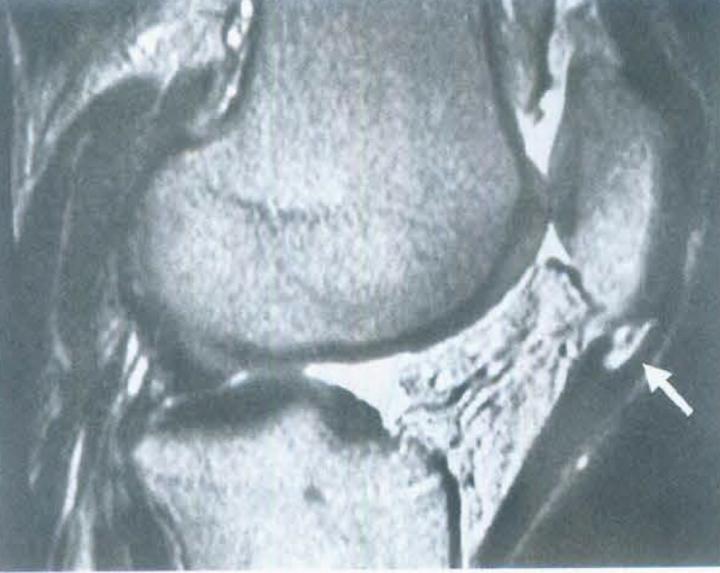

核磁共振检查,图中箭头所指部位为髌腱炎的好发部位